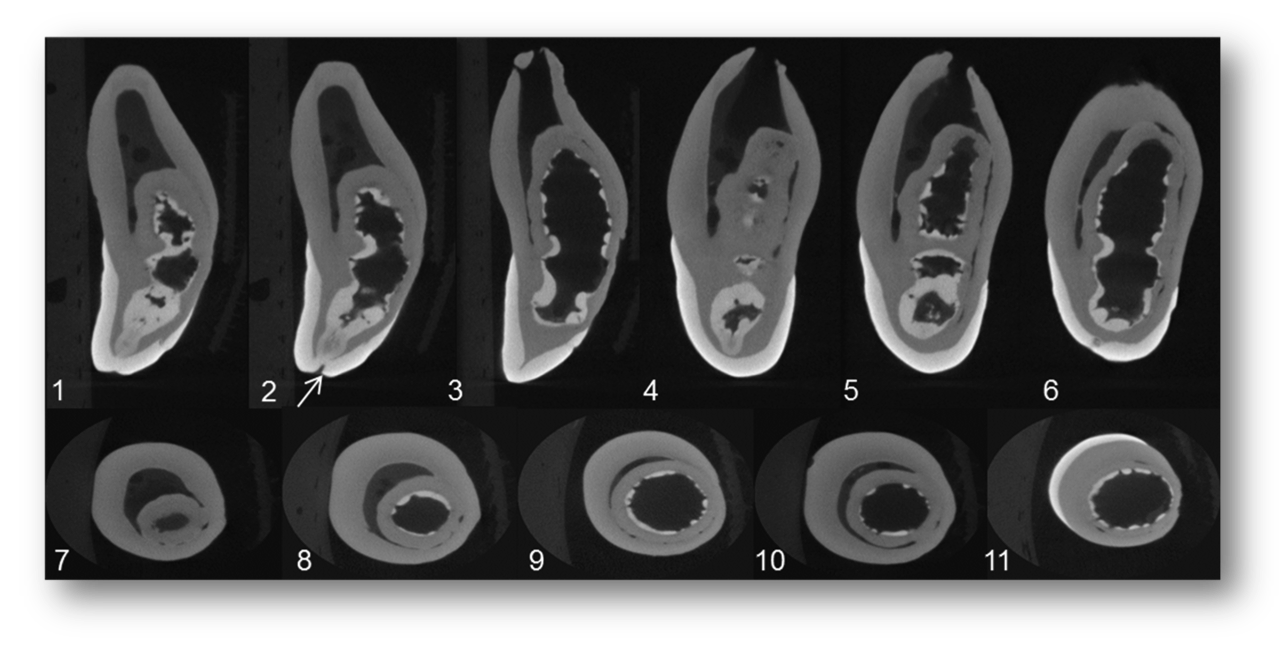

In-vitro analysis of extracted teeth

Micro Computed Tomography, or µCT, is an anatomical imaging technique that can provide three-dimensional images at very high spatial resolution. It is an imaging technology that can help in precise, highly accurate, and non-destructive in vitro analysis of teeth.